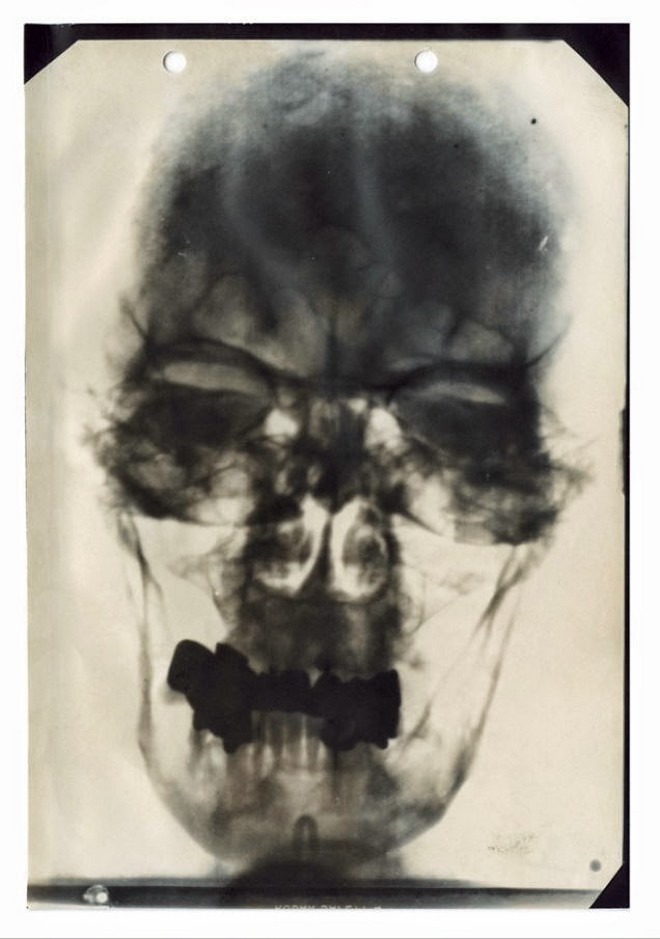

Μια ακτινογραφία της οδοντοστοιχίας του Χίτλερ το φθινόπωρο του 1944 μετά τη Συνωμοσία της 20ης Ιουλίου έδειχνε ξεκάθαρα το μεγάλο πρόβλημα που αντιμετώπιζε. Μόνο εκείνη τη χρονιά είχε βάλει 10 τεχνητά δόντια.

Από τα 32 ενήλικα δόντια του, μόλις τα πέντε ήταν δικά του. Τα υπόλοιπα ήταν θήκες στερεωμένες σε μια μεταλλική γέφυρα. Δεν είναι σίγουρο γιατί τα δόντια του Χίτλερ ήταν τόσο άσχημα, ωστόσο, οι περισσότεροι θεωρούν πως ένας σημαντικός παράγοντας ήταν η κακή διατροφή που ακολουθούσε τα χρόνια πριν από τον Μεγάλο Πόλεμο όταν ζούσε σε άθλιες συνθήκες.

Η ακτινογραφία με την οδοντοστοιχία του Χίτλερ το φθινόπωρο το 1944